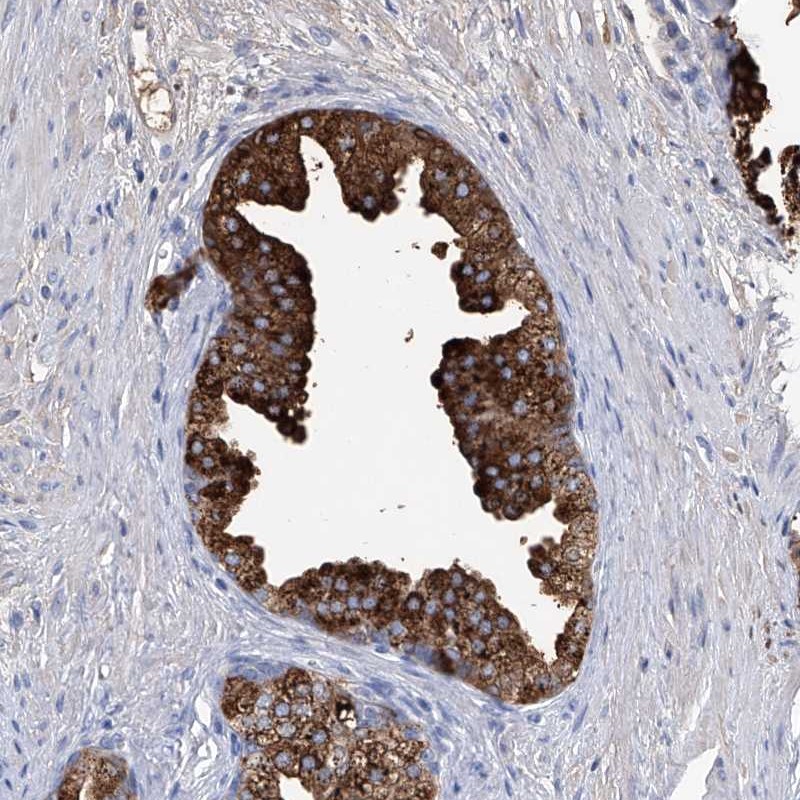

Immunohistochemical staining of human prostate shows strong cytoplasmic positivity in glandular cells.